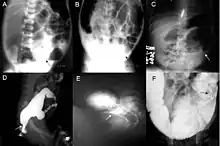

A: Plain abdominal radiograph showing a PARTZ at rectosigmoid, arrow. B: Plain abdominal radiograph showing a PARTZ at midsigmoid, arrow. C: Plain abdominal radiograph showing a PARTZ at descending colon, arrow. D: Contrast enema showing a CETZ at rectosigmoid, arrow. E: Contrast enema showing a CETZ at midsigmoid, arrow. F: Contrast enema showing a CETZ at descending colon, arrow.

Definitive diagnosis is made by suction biopsy of the distally narrowed segment.[30] A histologic examination of the tissue would show a lack of ganglionic nerve cells. Diagnostic techniques involve anorectal manometry,[31] barium enema, and rectal biopsy. The suction rectal biopsy is considered the current international gold standard in the diagnosis of Hirschsprung's disease.[32]

Radiologic findings may also assist with diagnosis.[33] Cineanography (fluoroscopy of contrast medium passing anorectal region) assists in determining the level of the affected intestines.[34]